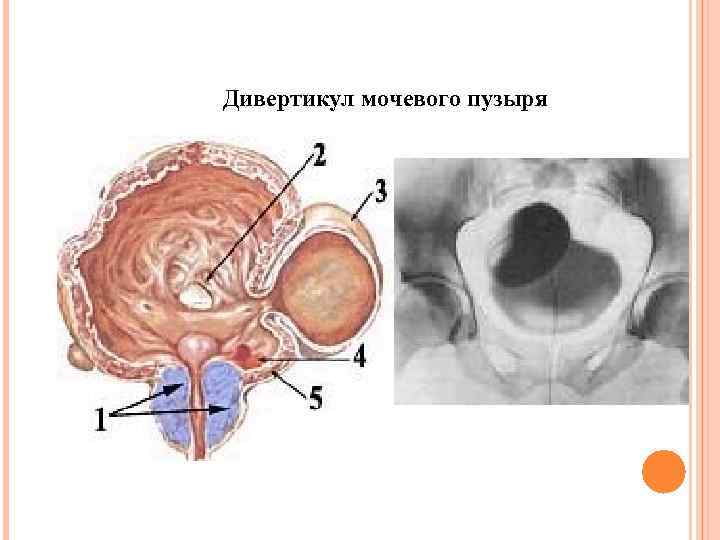

Дивертикул мочевого пузыря

Дивертикул мочевого пузыря